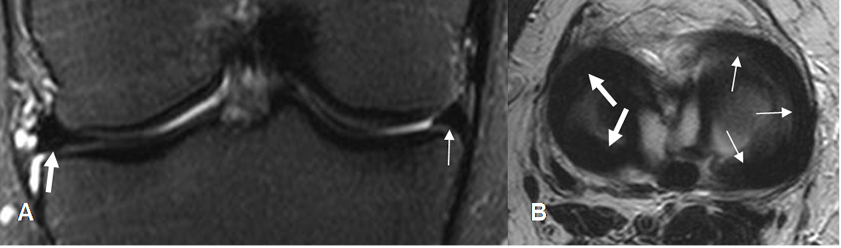

Fig 29. Meniscos normales.

A: RM sagital en T1, B: RM sagital en T2 y C: ArtroRM sagital en STIR. Meniscos normales triangulares e hipointensos en todas las secuencias. Cuernos anteriores (Flechas delgadas) y cuernos posteriores (Flechas gruesas).

Fig 30. Meniscos normales.

A: RM coronal en STIR. Menisco interno (Flecha delgada) y menisco externo (Flecha gruesa). B: RM axial en T2. Menisco interno (Flechas delgadas) y Externo (Flechas gruesas).

Fig 31. Meniscos normales en ArtroRM.

A: ArtroRM sagital en STIR y B: ArtroRM axial en STIR. Meniscos normales, rodeados por la mezcla de contraste hiperintensa.